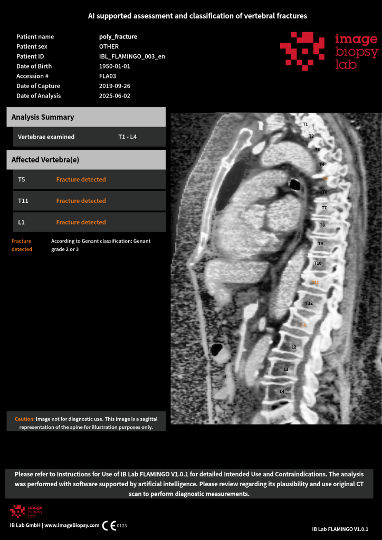

A black and white photo of a giraffe